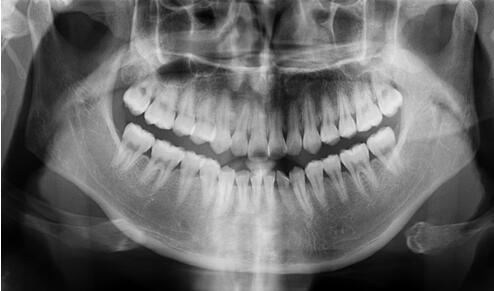

全口曲面斷層片

看似復(fù)雜,用人話說就是口腔牙齒的X光片。

牙醫(yī)通過對這張片的分析,能找出潛藏的牙周疾病問題、牙根發(fā)育等情況。通常是否拔牙、拔哪個牙、怎么拔,就是靠它了!